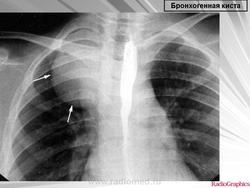

Рентгенологическая картина. При кисте, заполненной жидкостью, обнаруживается округлое или овальное затенение с четкими контурами. Контуры затенения могут изменяться в зависимости от фазы дыхания. При бронхогенной кисте, заполненной воздухом, видна правильной формы полость с чрезвычайно четким контуром, на фоне которой легочный рисунок обычно ослаблен. Более отчетливо просветление прослеживается на томограммах. Небольшой уровень жидкости на дне наблюдается не всегда, однако этот симптом, весьма важен с точки зрения дифференциальной диагностики истинных бронхогенных кист, продуцирующих секрет, от воздушных полостей другого происхождения (булл). Бронхография. Контраст не всегда попадает в полость из-за чрезвычайно узкого сообщения последней с просветом бронхиального дерева.

ID: 8561 Bronchogenic cyst Dr Frank Gaillard - 11 Feb 2010 Chest x-ray of a 40 year old woman demonstrates a founded well circumscr...

ID: 6313 Bronchogenic cyst Dr Frank Gaillard - 4 Jun 2009 Retrocardiac bronchogenic cyst only well seen on AP CXR with expiration.